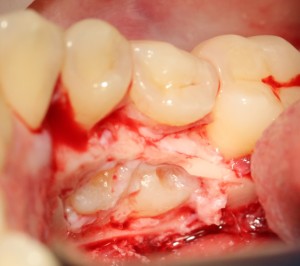

А вот они! Далее мы руководствуемся главным правилом хирурга-стоматолога:

При удалении зубов нельзя прилагать значительных физических усилий. Если операция идет правильно, зубы должны, вообще, сами вываливаться из лунок.

Однако, наши сверхкомплектные зубы вываливаться не хотят. Потому что их коронки образуют что-то вроде клина, который непросто вытащить через маленькое трепанационное отверстие.

Поэтому мы, всё также, с помощью ультразвука, отпиливаем коронку одного из зубов:

После чего, зубы вываливаются из лунок самостоятельно. В прямом смысле слова: